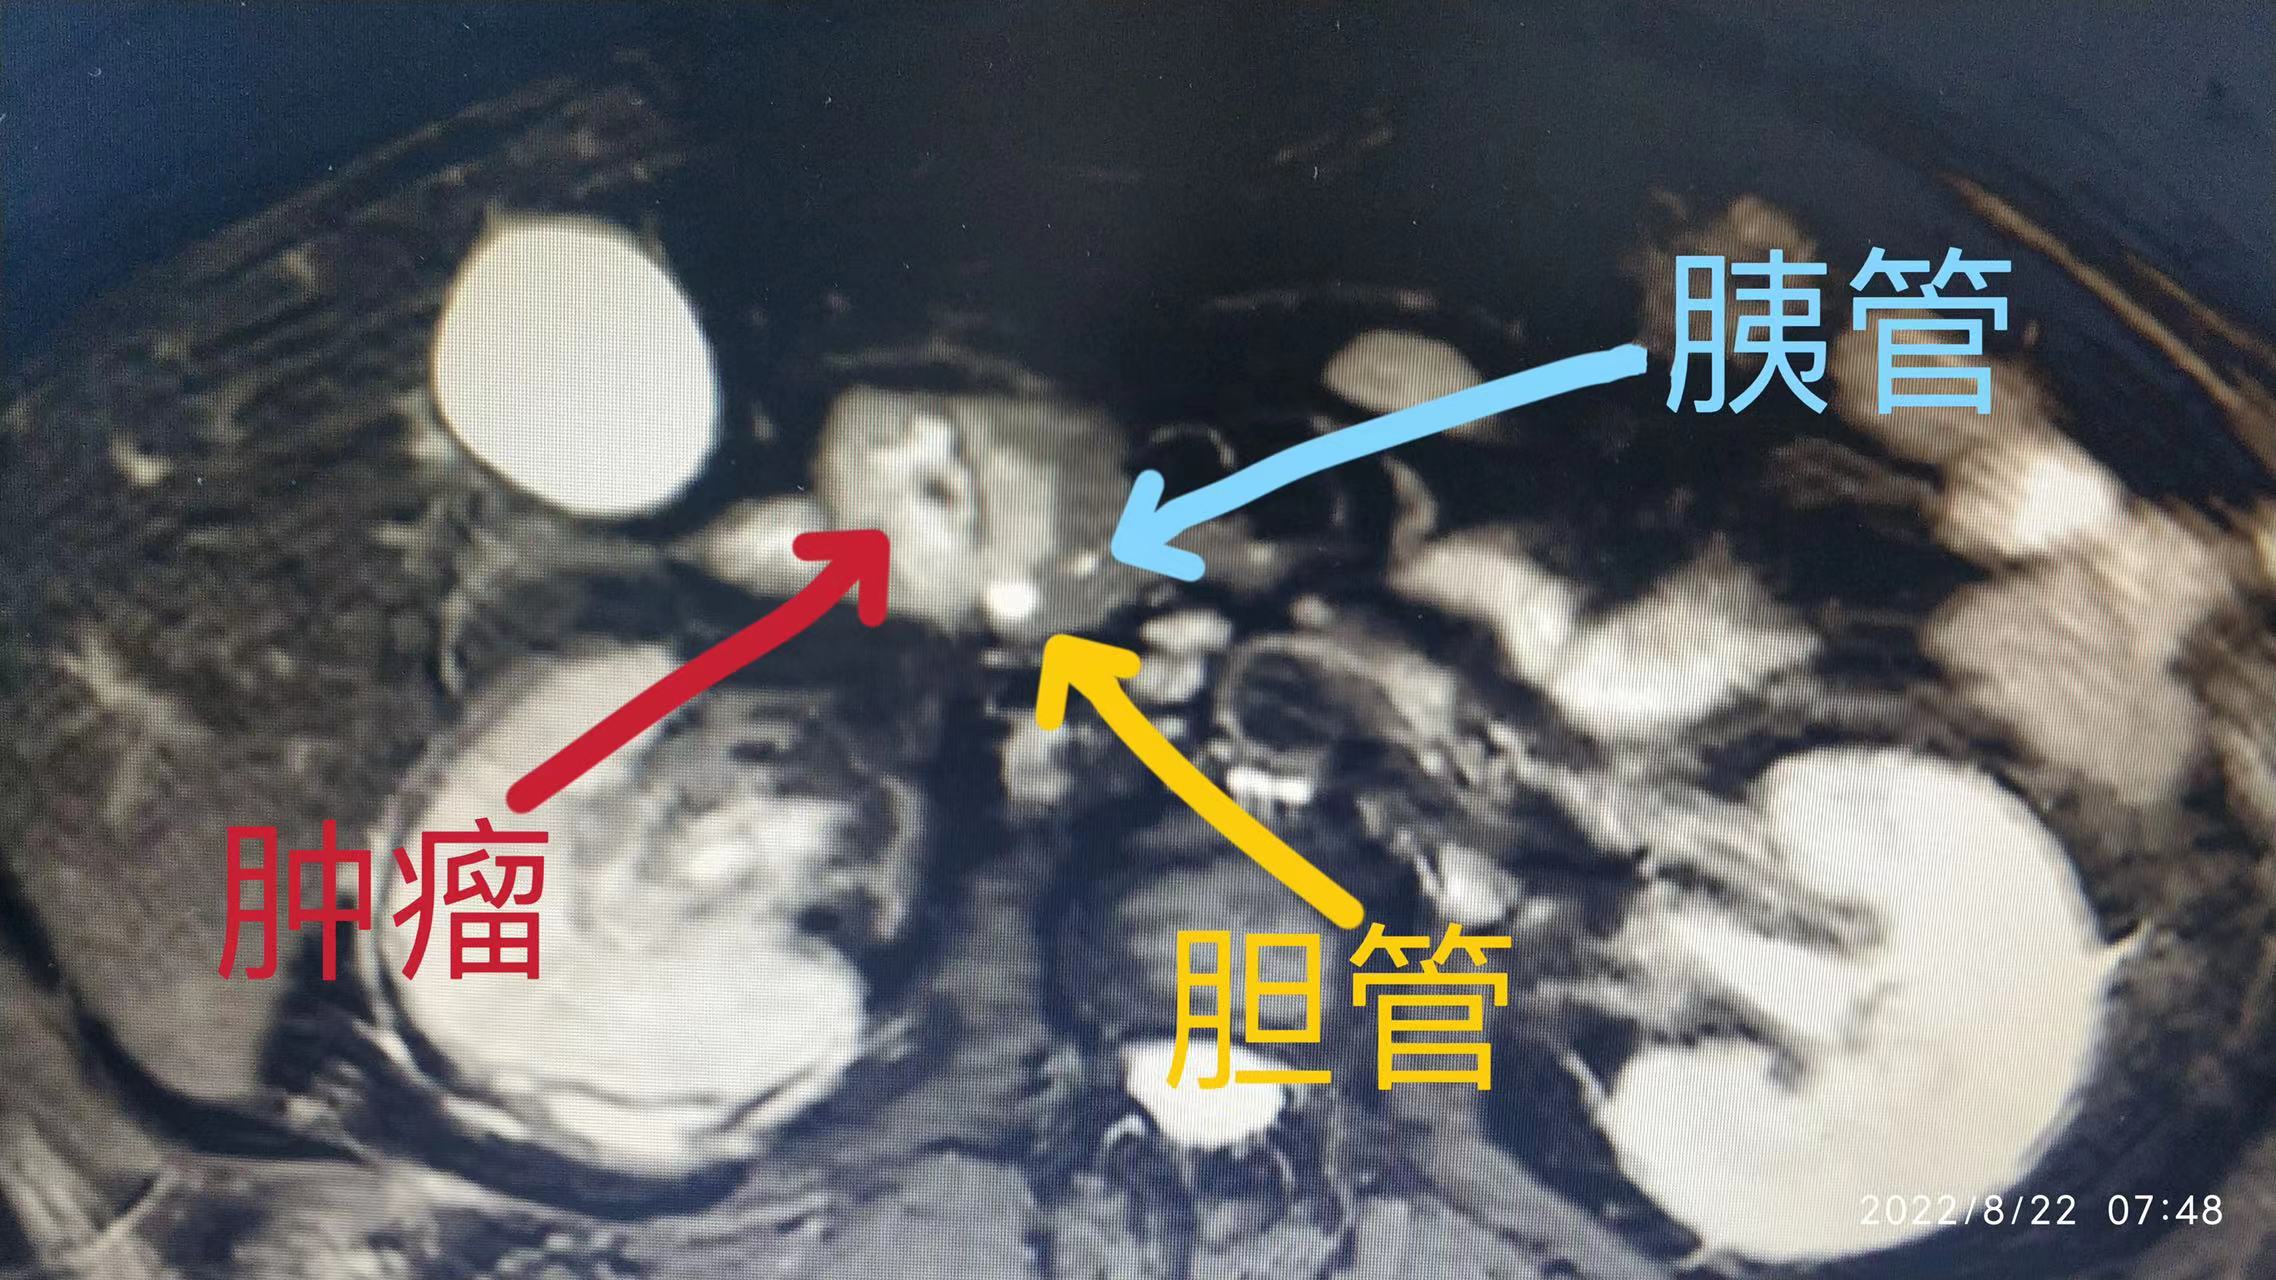

可罗阿姨的胰头部实性假乳头状瘤位置紧邻胆管和主胰管,进行微创局部切除肿瘤的手术难度很大。“手术操作时,在完整切除胰头肿瘤的同时,还要防止损伤邻近的胆管和主胰管,如果损伤了胆管和主胰管,从而导致胰漏与胆漏,进而多种消化酶(胰腺淀粉酶、胰腺蛋白酶等)漏于腹腔,引起腹腔感染,腐蚀周边血管,造成严重的出血,将危及患者生命。” 彭钊说。